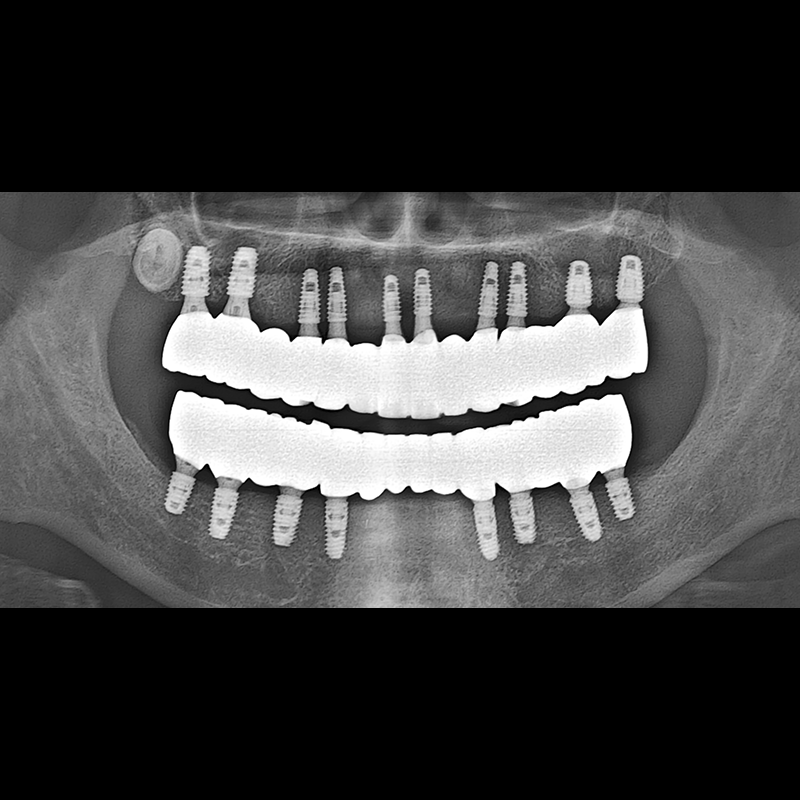

BEFORE AFTER

Implant before and after 2025.05.30

Implants were placed in the missing tooth and in the tooth position where it was difficult to save.